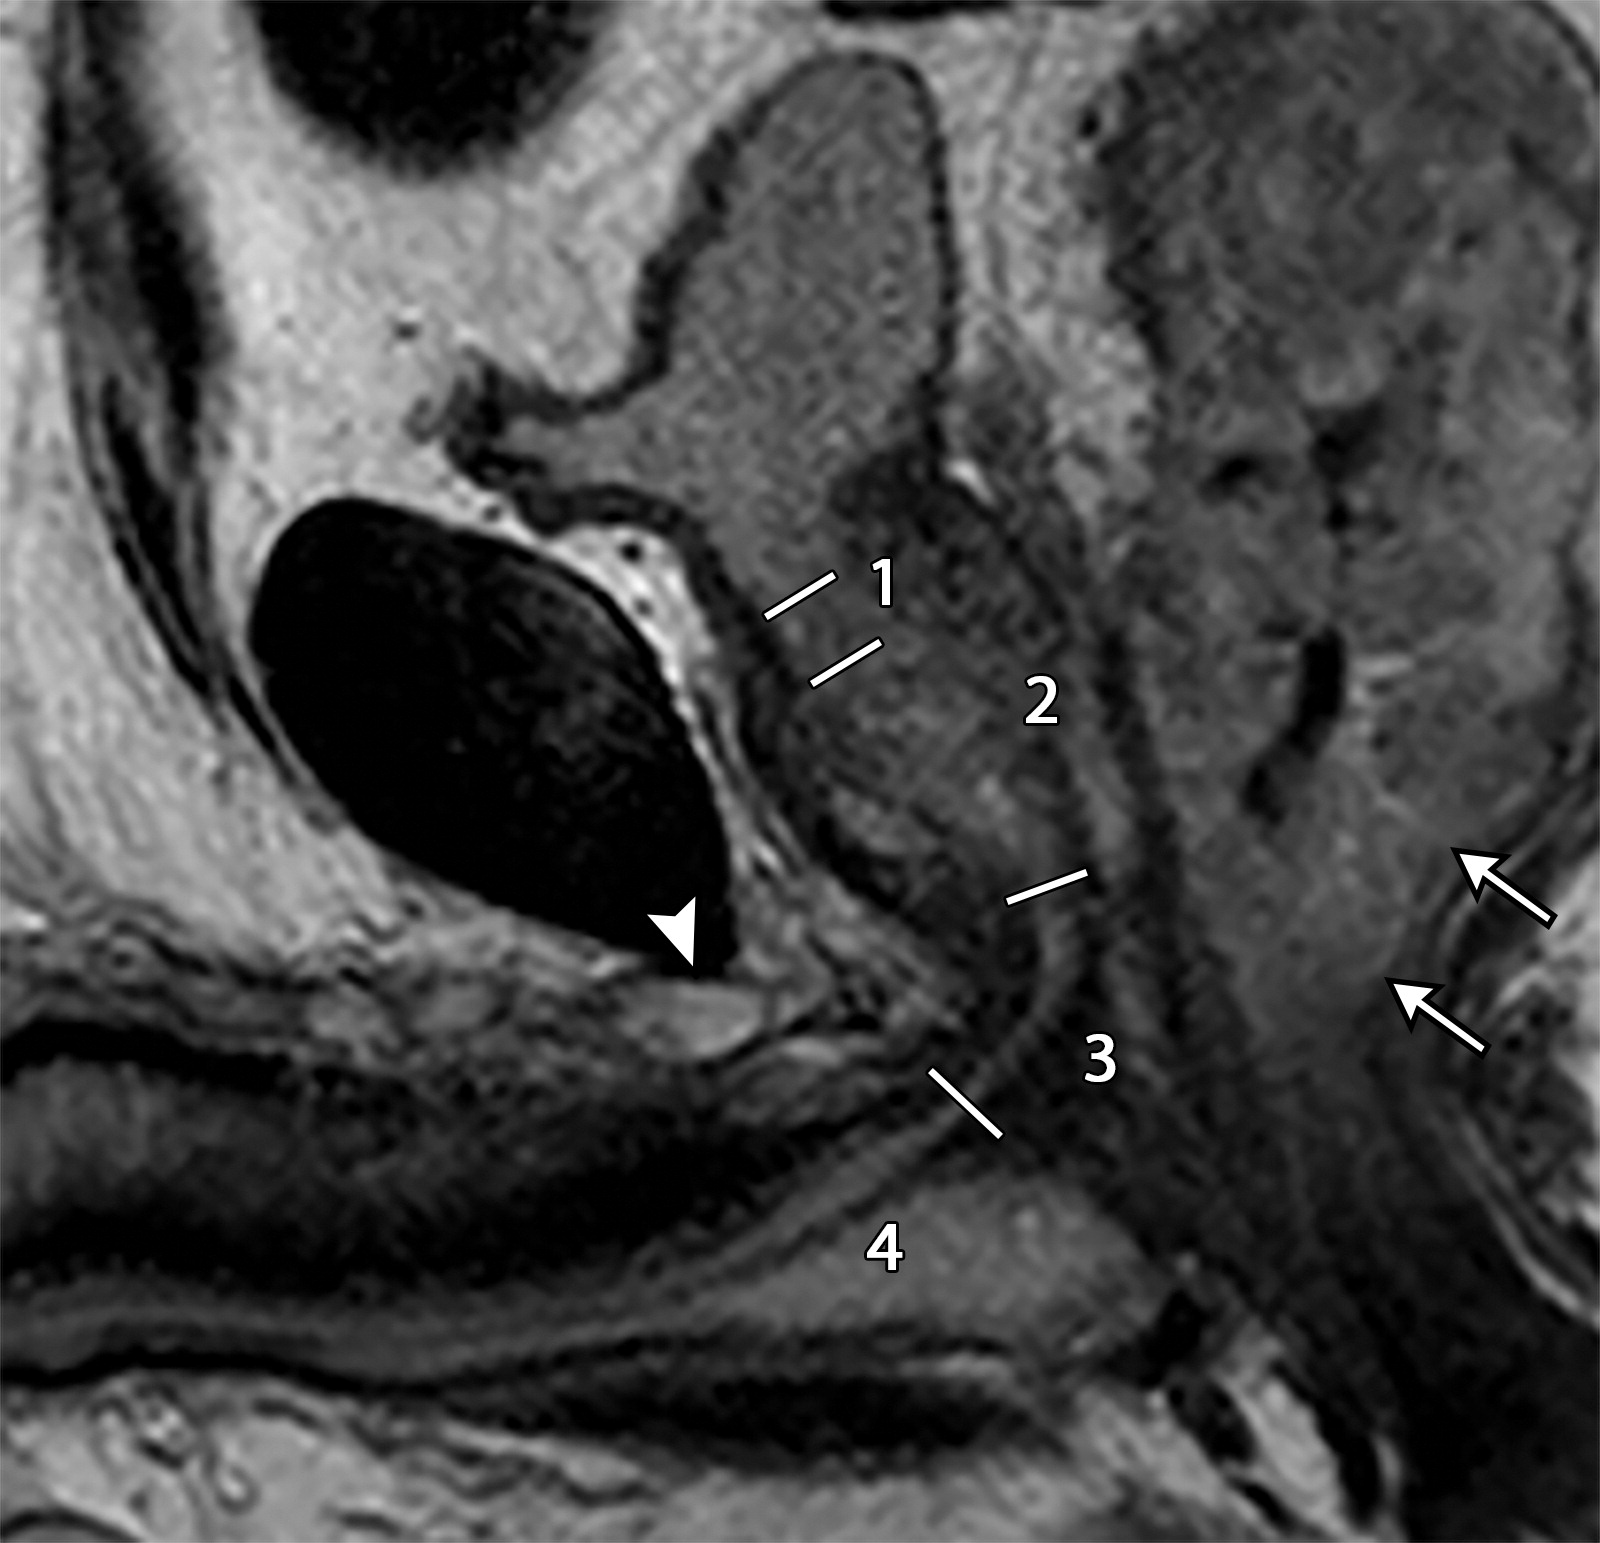

6d6d81d3c968fb4da4c4e0914b865b2a.jpeg阴茎背侧静脉的血栓栓塞。

一个偶然发现的血栓,导致阴茎背静脉的正常血流流空信号消失,伴近端不规则扩张(白色短箭头),白色长箭头标识直肠癌。图中标注了尿道的四个部分,1=前列腺前部,2=前列腺部,3=膜部,4=海绵体部。